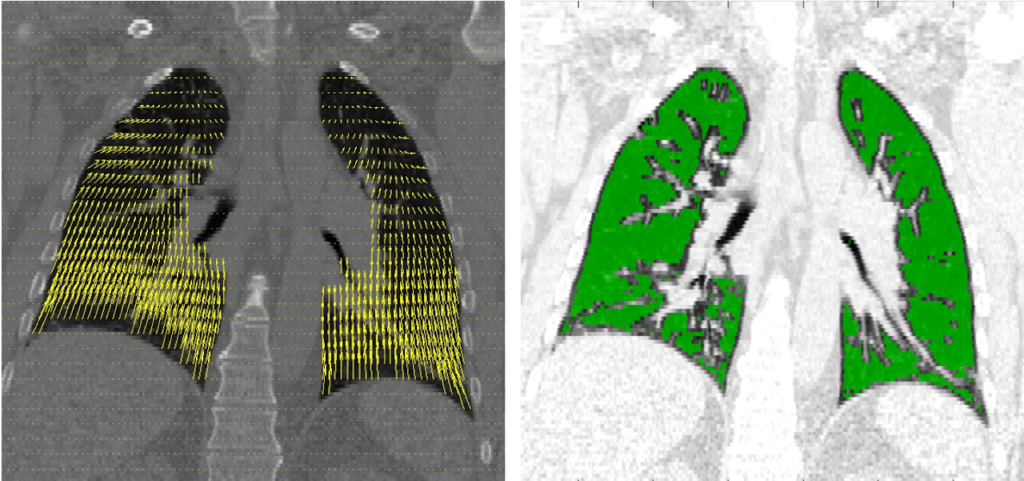

Most medical image analysis applications require pre-processing steps including image segmentation (right) and deformable image registration (left). Registration is of particular importance the DMIC’s work on inferring patient-specific biomechanical properties from dynamic imaging.